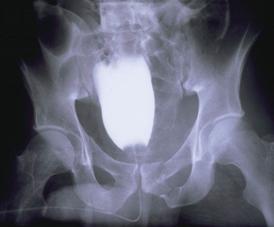

Banda de stabilizare Dallas Fractura de bazin. Radiografie in

incidenta AP

Inaintea

aplicarii benzii de stabilizare Dallas

Fractura de bazin

. Radiografie in incidenta AP Fractura de spina

iliaca antero-superioara

Dupa aplicarea benzii de stabilizare Dallas prin avulsie. - Stabila -